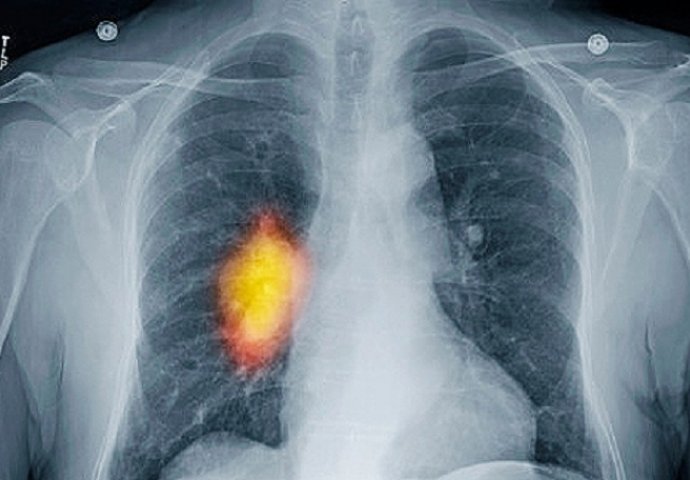

PRVI SIMPTOMI RAKA PLUĆA: Ako imate nešto od navedenoga, ODMAH DOKTORU

Mnogi ljudi rak pluća odmah povezuju sa smrću, što je na neki način prihvatljivo, obzirom da godišnje veliki broj ljudi umire od raka pluća.

Kada se rak pluća otkrije dovoljno rano, on se može izliječiti.

Rak pluća koji je otkriven u ranom stadiju je izliječiv kod 50 posto slučajeva, u poređenju s rakom koji je već metastazirao, gde je izlečivost tek oko 2 posto. Obratite pažnju na prve simptome raka pluća kako bi vjerovatnoća izliječenja bila što veća.